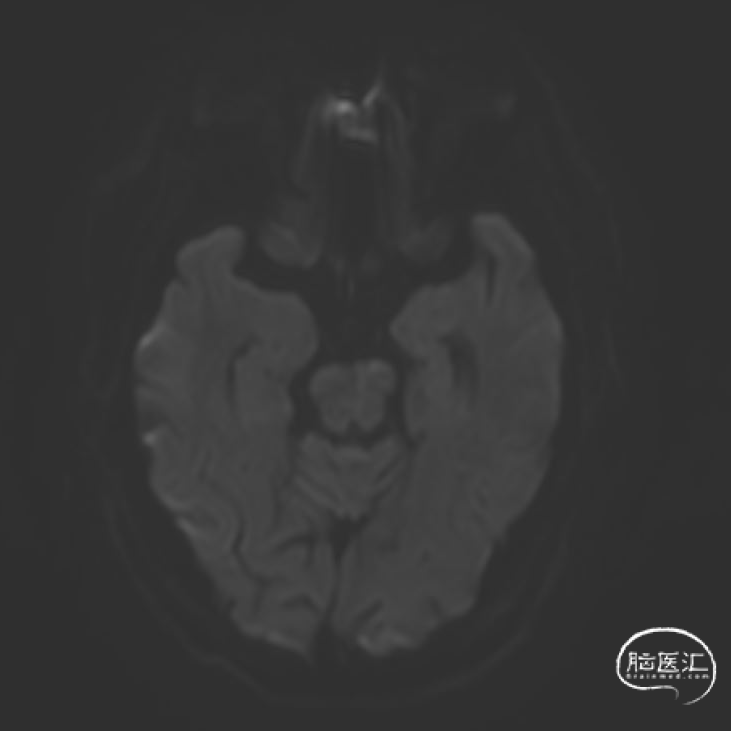

➢2023年10月31日

头颅MRI平扫:脑桥、左侧小脑半球、颞叶多发急性/亚急性脑梗死。

➢2023年11月06日

头颅MRI平扫:脑桥、左侧中脑、左侧桥臂急性脑梗死。

➢2023年11月14日

头颅MRI平扫+HRMRI:脑桥、中脑急性/亚急性脑梗死;双侧桥臂变性。

HRMRI:基底动脉闭塞并斑块合并局部出血;左侧大脑后动脉P1段斑块形成,相应管腔闭塞,左侧椎动脉V2-V4段斑块形成,相应管腔中重度狭窄,左侧椎动脉V4段管壁弥漫性增厚,相应管腔中度狭窄;右侧大脑后动脉纤细。